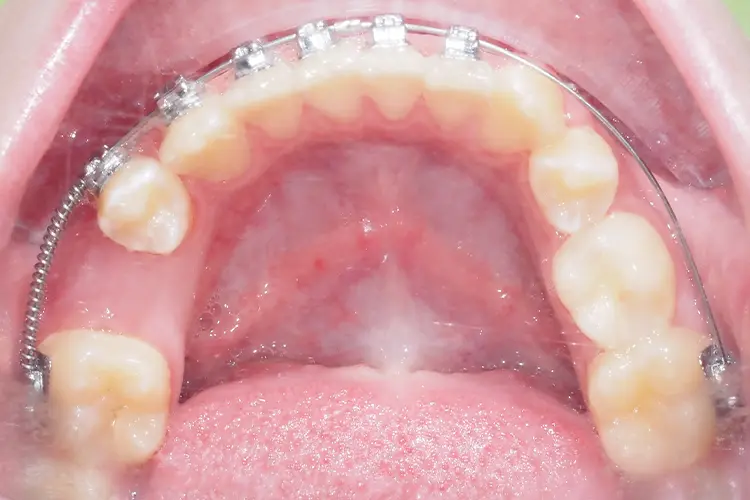

• Częściowych lub pełnych aparatów stałych, które stopniowo przesuwają zęby i odtwarzają właściwą przestrzeń.

efekt leczenia ortodontycznego